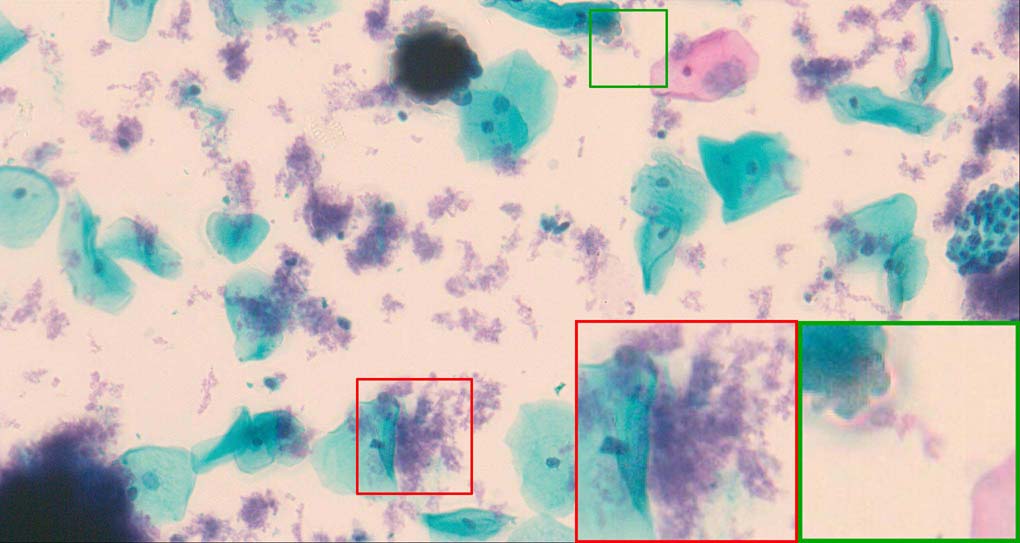

To demonstrate the effectiveness and efficiency of the proposed image fusion method , we conduct a set of comparative experiments on three image datasets. The first is composed by 8 pairs of multi-modal medical images and the second one contains 15 pairs of multi-focus gray or color natural images. These two datasets are often used in many related papers and some examples are shown in Figure 3(a) and Figure 3(b). The third one is a new multi-focus cervical cell image dataset collected by ourselves, which consists of 15 groups of color images and each group contains a series of multi-focus cervix cell images with size of or , etc. Some source examples are shown in Figure 3(c). Our source code implemented in C++ along with the new multi-focus cervical cell image dataset is available online.

Figure 9, Figure 10 and Figure 11 show the comparative fused results of the multi-focus cell images shown in Figure 3(c). For clarity, we also present a closeup view in the right-bottom of each sub-picture in Figure 9 and Figure 10. As shown in the close-up views of Figure 9, the fused images based on DSIFT, IM, MWGF and BF methods are extremely blurred in the boundary and fail to keep the details of cell nucleus. Furthermore, the DTCWT and NSCT based methods produce halo artifacts in the fused images, while GFF and CNN based methods fail to preserve the small cell nucleus. LP-SR based method nearly works fine which keeps the most of the details of the small size cells, but the integrity of the clustered large size cells is damaged. Fortunately, in our proposed method, the integrity of the clustered large size cells is preserved and most of the isolated small size cells are maintained from the original images, which demonstrates the best visual quality.

Similarly, as shown in the close-up views of Figure 10, the fused images from DSIFT, IM, MWGF and BF are blurred and lose some nucleus details, while the results from DTCWT, GFF, CNN and NSCT produce halo artifacts. LP-SR based method can keep details well but also produces halo artifacts and other noise. Our method can preserve the focused areas of different source images well without introducing any artifacts. For the example illustrated in Figure 11, the fused images generated by DSIFT, DTCWT, IM and NSCT all fail to preserve the focused areas of different source images and result in extremely blurred images. The GFF, CNN, MWGF and BF based method introduces a lot of color distortion of the nucleus regions and the obvious halo artifact. The result of LP-SR based method is close to the one of our method but introduces some odd color distortion. Again, our method produces fused image which can preserve the focused areas of different source images well without introducing any artifacts.